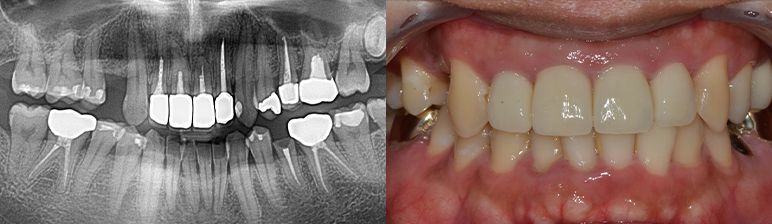

CASE 01

-

치료 전 -

치료 후